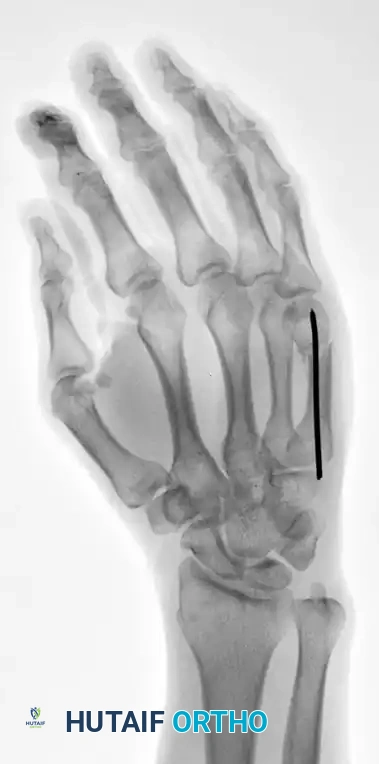

This technique is equally effective for mid-shaft fractures, as demonstrated in the fourth metacarpal example below:

FIGURE 67-37A: Preoperative AP radiograph of a fourth metacarpal shaft fracture.

FIGURE 67-37B: Preoperative lateral radiograph of the fourth metacarpal fracture.

FIGURE 67-37C: Postoperative AP radiograph showing intramedullary fixation with a Kirschner wire.

FIGURE 67-37D: Postoperative lateral radiograph confirming anatomic restoration.